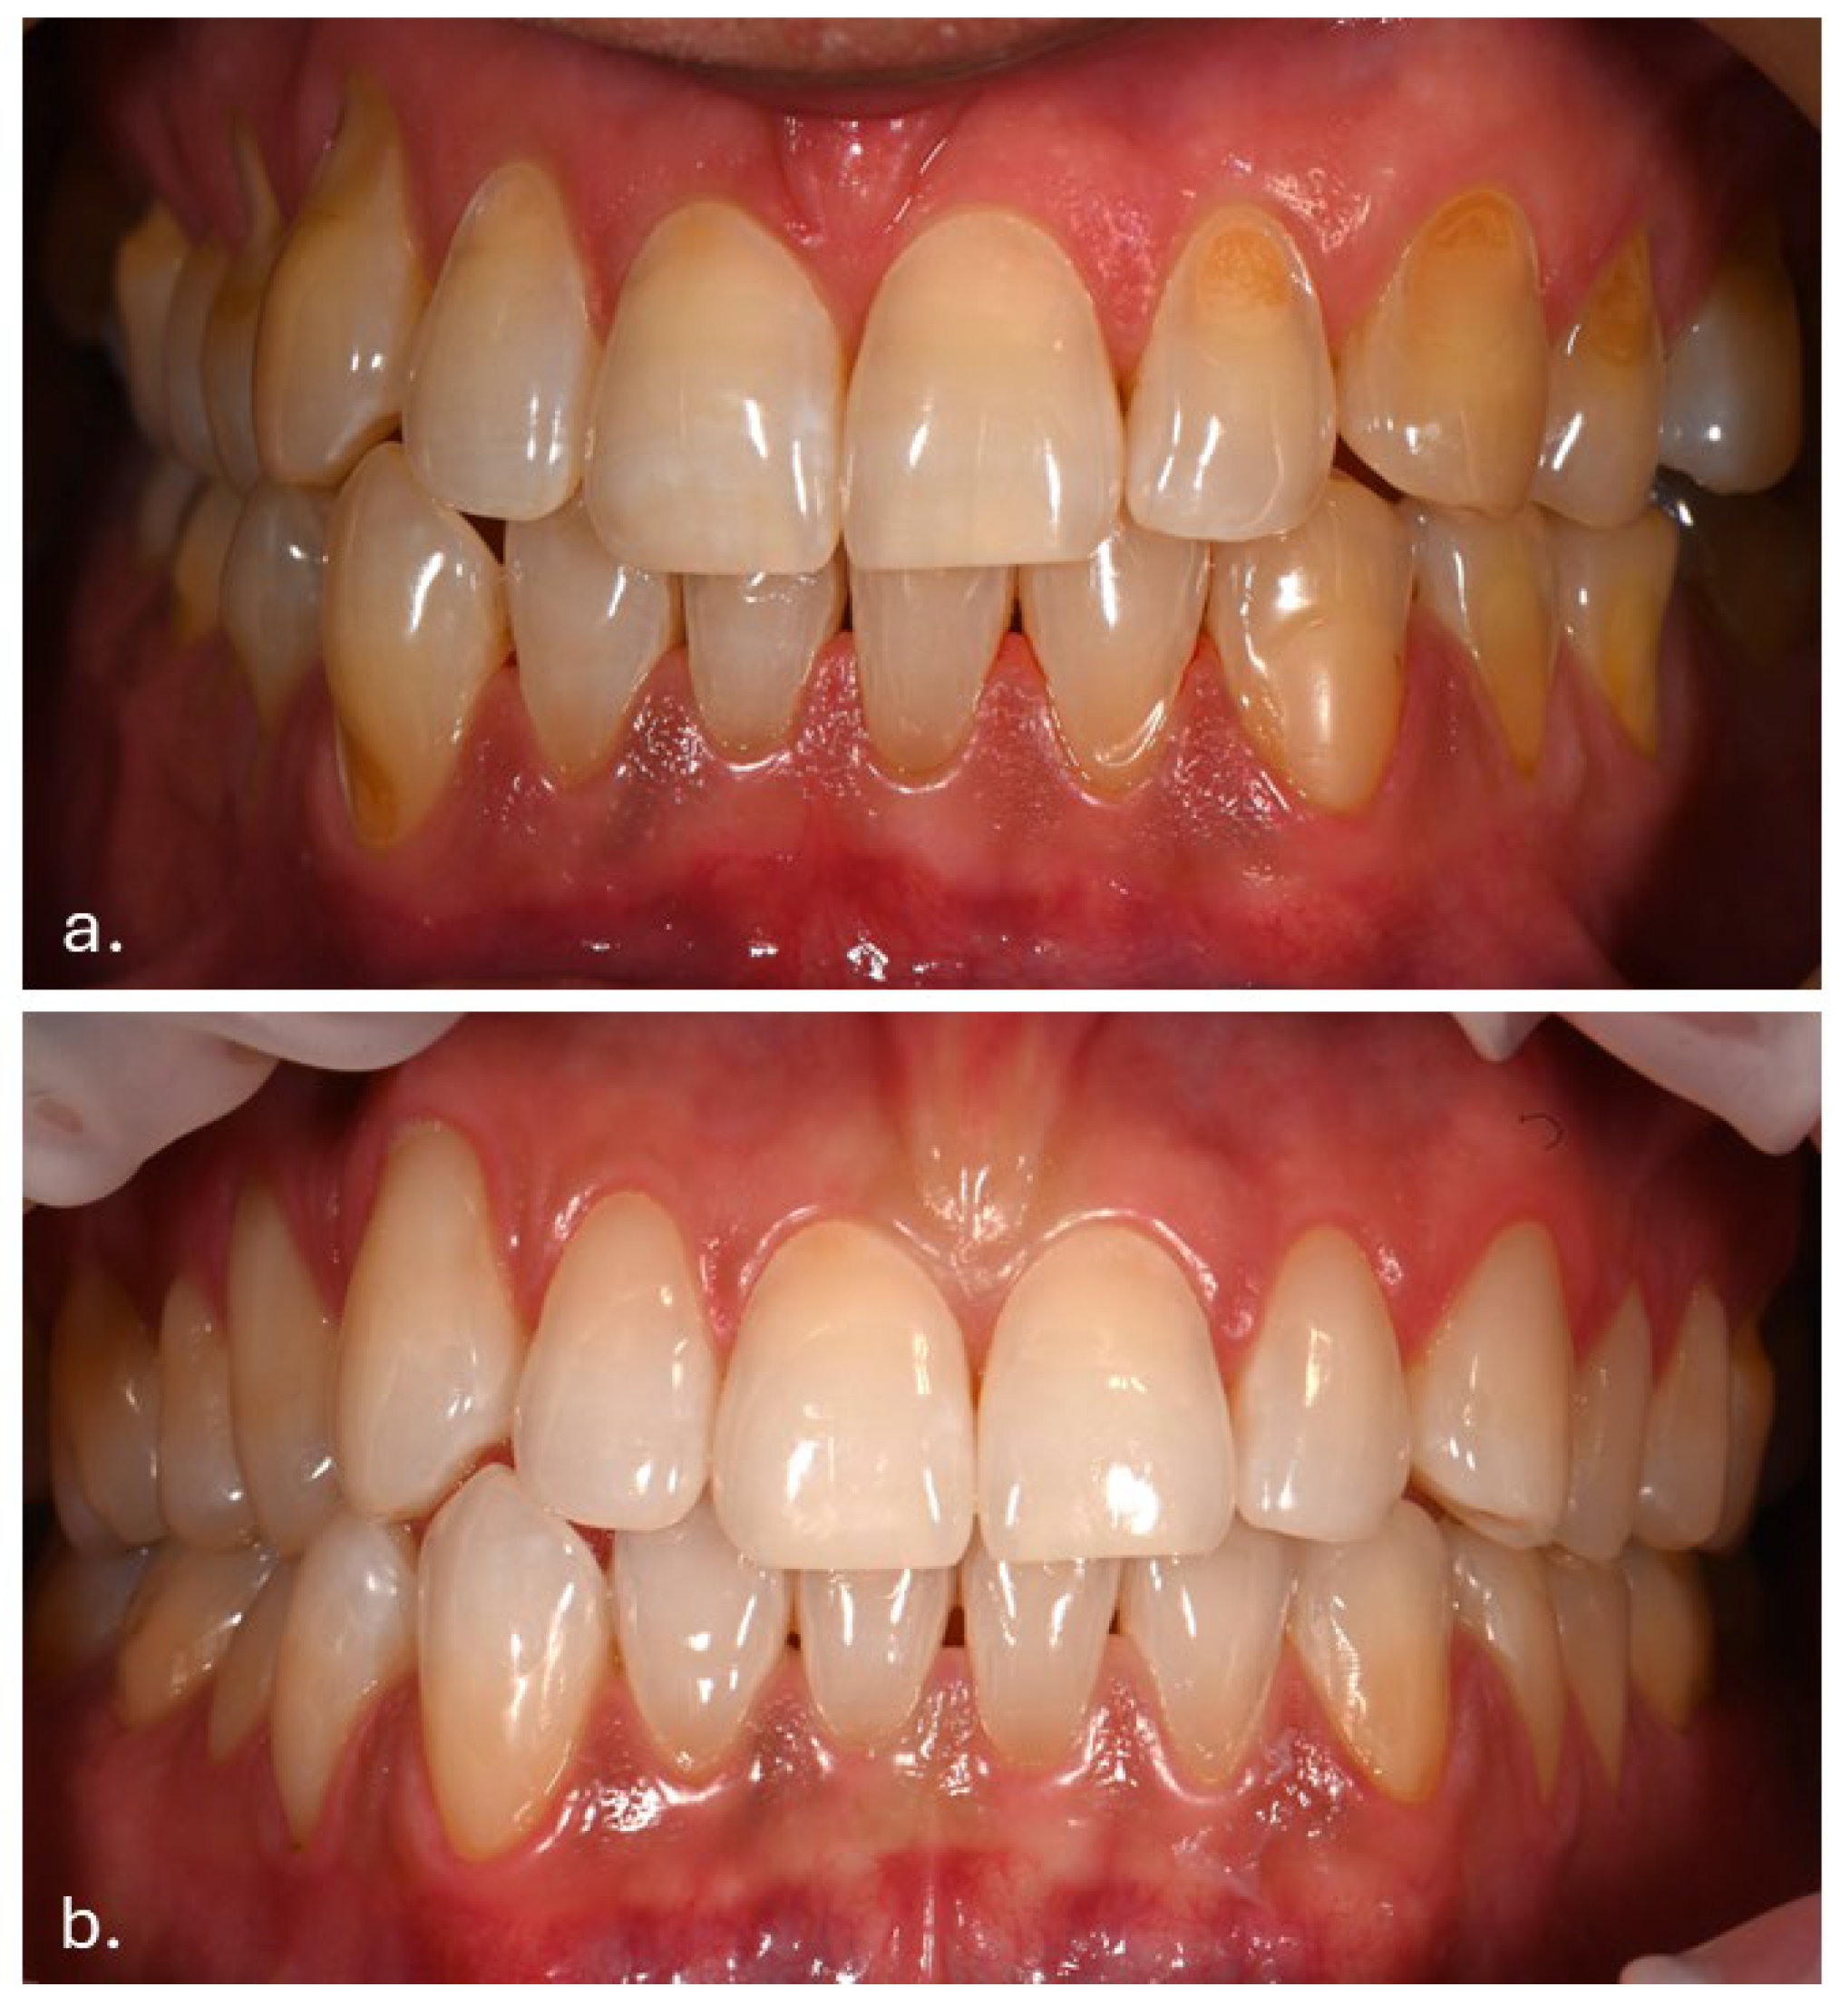

The patient had previously received treatment at the same practice and was familiar to the dental team. Several cervical abfractions had been restored with composite resin restorations. During these earlier visits two years ago, a slight brown pigmentation was noted on the attached gingiva in the lower anterior region. In contrast, the gingiva of the maxillary arch and the oral mucosa in other regions appeared clinically normal, with no evidence of pigmentation (Figure 1).

Figure 1.

(a) Intraoral photograph taken during the patient’s initial examination, showing cervical abfractions. (b) Post-treatment photograph following restoration of the abfractions with direct composite resin.

Intraoral examination revealed brown pigmentation of the attached gingiva in both the maxillary and mandibular arches. The lesions were almost symmetrically distributed and more intensive in color in the anterior region of the lower jaw. Areas with previously observed pigmentation appeared darker in color and showed an increase in surface area. The pigmentation did not extend to the tips of the interdental papillae (Figure 2).

Figure 2.

Symmetrical brown pigmentation of the attached gingiva during the Melanotan II therapy: (a). frontal view; (b). lateral view.